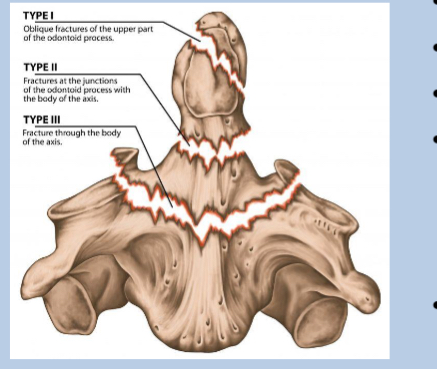

What does type 1 of odontoid peg fracture look like?

superior to the base

What does type 2 of odontoid peg fracture look like?

Transverse through the base

What does type 3 of odontoid peg fracture look like?

below base into the body